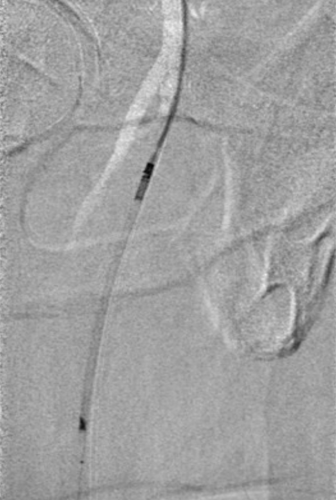

腘动脉、胫腓干的短段闭塞

★ 巧克力球囊

股浅动脉、

腘动脉与胫腓干病变

ELUVIA™ 6-120mm,6-80mm用于股浅

Chocolate 4-150mm, Sterling™ 4-20mm,

DCB 4-150mm